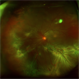

- Andrea E. Arriola-López MD MSc

Fundus camera

OPTOS Dakota - Description

- 56-year-old man, BCVA 20/25. Incidental finding. Laser was given.